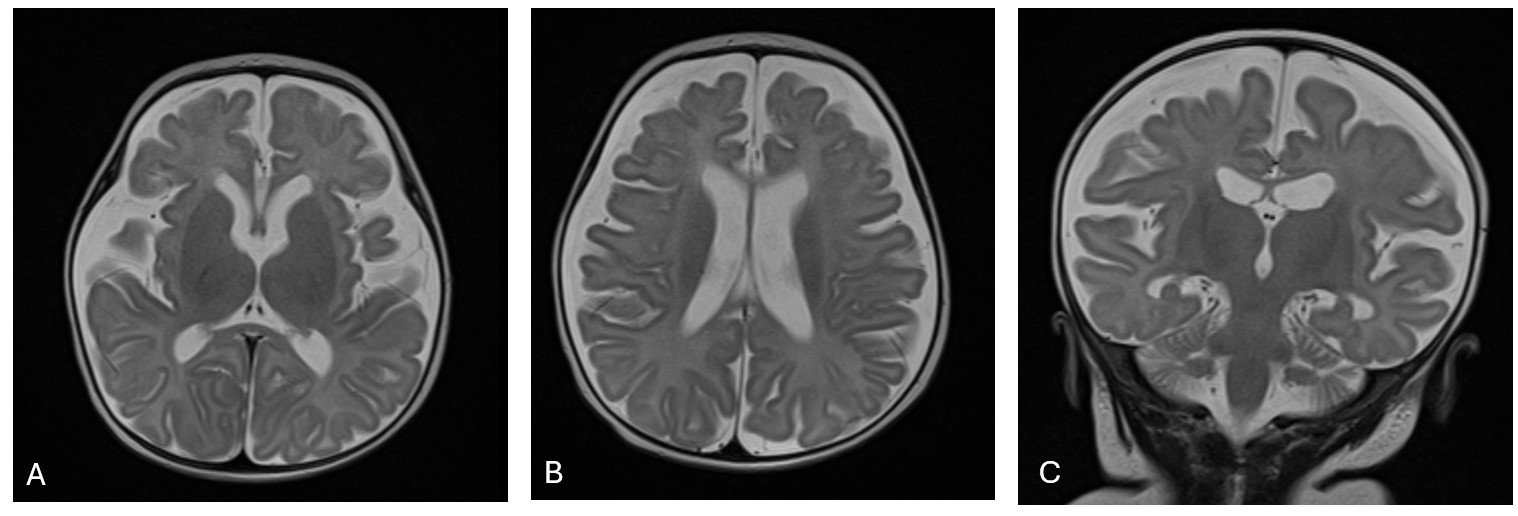

The second brain MRI was performed on a 3-month-old infant with history of intrauterine growth restriction (IUGR), born pre-term at 34 weeks gestation, who was hospitalized for respiratory distress and brief cardiac arrest. The brain MRI demonstrated diffuse cerebral white matter atrophy with preserved grey matter, bilateral subdural cerebrospinal (CSF) collections and diffuse enlargement of the subarachnoid spaces. Ventricles were within normal size, and no evidence of acute hemorrhage was observed (Figure2).

MRI brain T2 image of a 3-month-old NLE infant, pre-term at 34 weeks gestation

Axial T2 images (A & B) and coronal T2 images (C) demonstrated brain diffuse cerebral white matter atrophy with preserved grey matter, and diffuse enlargement of the subarachnoid spaces. (C) bilateral subdural CSF collections.